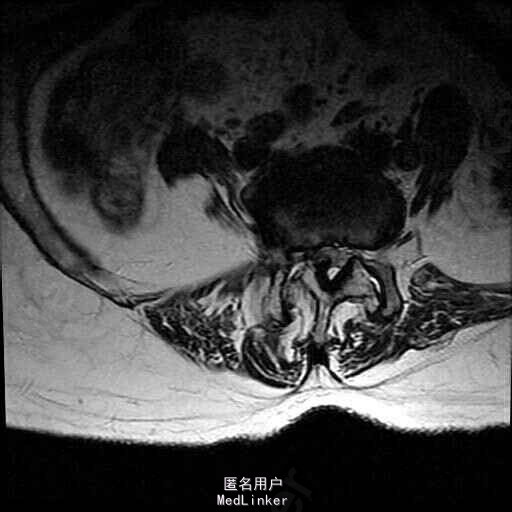

查体:脊柱侧弯,上肢无麻木,疼痛感觉异常,腰部右侧疼痛,右下肢及右臀部疼痛,麻木感。双侧肌力及肌张力可,膝腱反射(+),踝反射(+),病理征(—),直腿抬高试验。右侧40度,左侧55度。 辅助检查:腰椎x线片:腰椎侧弯,腰椎退行性改变,L5椎体略行前滑脱 脊柱全长:胸腰段呈S形,L5椎体向前滑脱,L3椎体略变扁,颈胸腰椎退行性改变 MRI:脊柱侧弯,L2-3,L3-L4,L4-L5,L5-S1椎间盘突出,相应节段椎管狭窄

诊断:腰椎侧弯,腰椎椎管狭窄 治疗:手术矫形:早期侧路减压融合,后期再行后路固定。